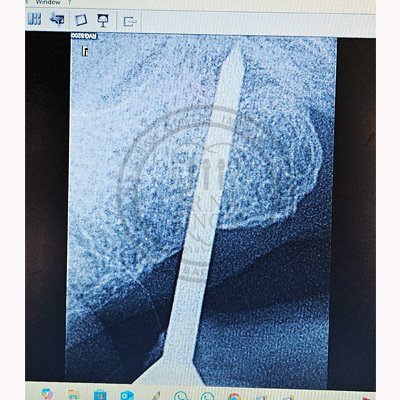

Case – 11 Baleram